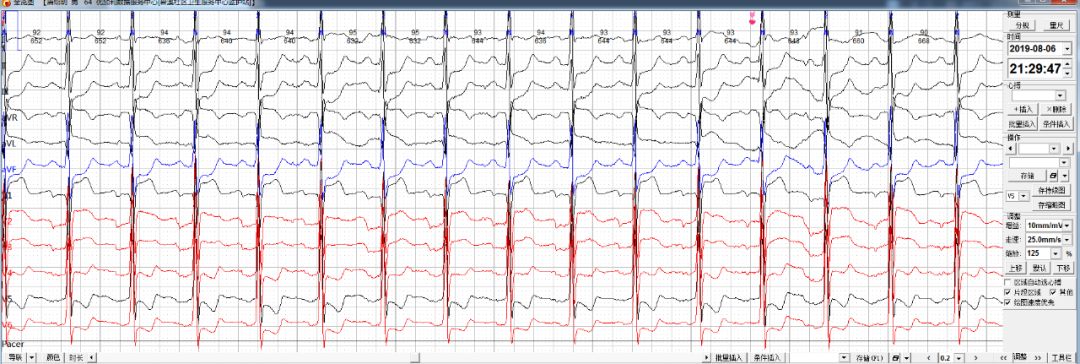

每日一图丨NO.664 同一患者出现如下六幅心电图改变,如何判断?乐普医疗AI关注2021-01-20 14:14 心电图解析(NO.663)今日读图(NO.664)患者姜某,男性,66岁。佩戴心安宝24小时动态心电监护仪,监测到如下片段如何分析诊断?诊断完毕后要记得将答案写在留言区哦 浏览 51点赞 评论 收藏 分享 手机扫一扫分享分享 举报 评论图片表情视频评价全部评论推荐 每日一图丨NO.658 患者的心电图出现如下改变,请诊断?乐普医疗AI0每日一图丨NO.682 患者出现如下心电改变,如何诊断?乐普医疗AI0每日一图丨NO.646 患者出现如下心电改变,如何诊断?乐普医疗AI0每日一图丨NO.654 如下三幅心电图出自同一位患者,该如何诊断?乐普医疗AI0每日一图丨NO.680 窦性心律患者出现如下心电改变,如何诊断?乐普医疗AI0每日一图丨NO.643 26岁女性患者心电图改变如何诊断?乐普医疗AI0每日一图丨NO.637 这位患者心电图如何诊断?乐普医疗AI0每日一图丨NO.635 两幅图同一患者出现如下心电变化该如何诊断?乐普医疗AI0每日一图丨NO.675 请判断患者出现何种心电异常改变?乐普医疗AI0每日一图丨NO.678 71岁男性患者出现如下心电改变,请分析。乐普医疗AI0点赞 评论 收藏 分享 手机扫一扫分享分享 举报